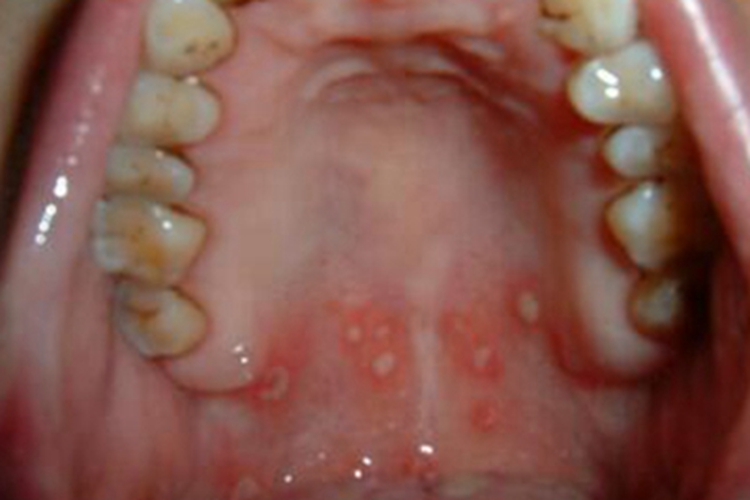

二期口腔梅毒患者口腔黏膜充血,有弥漫性潮红,可出现梅毒黏膜斑,是二期梅毒最常见的口腔损害。损害呈灰白色、光亮而微隆的斑块,圆形或椭圆形,直径约1cm,边界清楚。易发生浅表溃疡,表面覆盖灰白色假膜,周围有红晕。